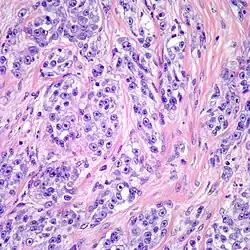

| Clear cell sarcoma. Tumor cells with prominent nucleoli and clear cytoplasm are arranged in well-defined nests surrounded by dense fibrous stroma. | |

Despite the name clear cell sarcoma, the tumor cells do not necessarily need to have clear cytoplasm. The lesion has a distinctly nested growth pattern with a mixture of spindle, epithelioid and tumor giant cells. Approximately two thirds of the tumors contain melanin pigment. Clear cell sarcoma, similar to melanoma, has consistent positivity for S-100, HMB-45, and MITF.[6]